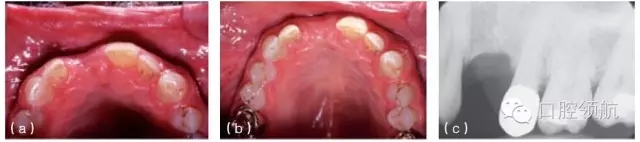

圖10.2 (a)治療前缺牙區(qū)的切面觀,可見唇側(cè)有骨缺損。(b)缺牙區(qū)植骨后的切面觀,可見唇側(cè)牙槽嵴厚度增加。(c)治療前X線片顯示上頜第一前磨牙的拔牙區(qū)有較大骨缺損。(d)植骨后植入種植體。(e)由于種植體植入前對(duì)骨缺損區(qū)進(jìn)行植骨,第一前磨牙的冠在高度和頰側(cè)面的位置都接近正常。